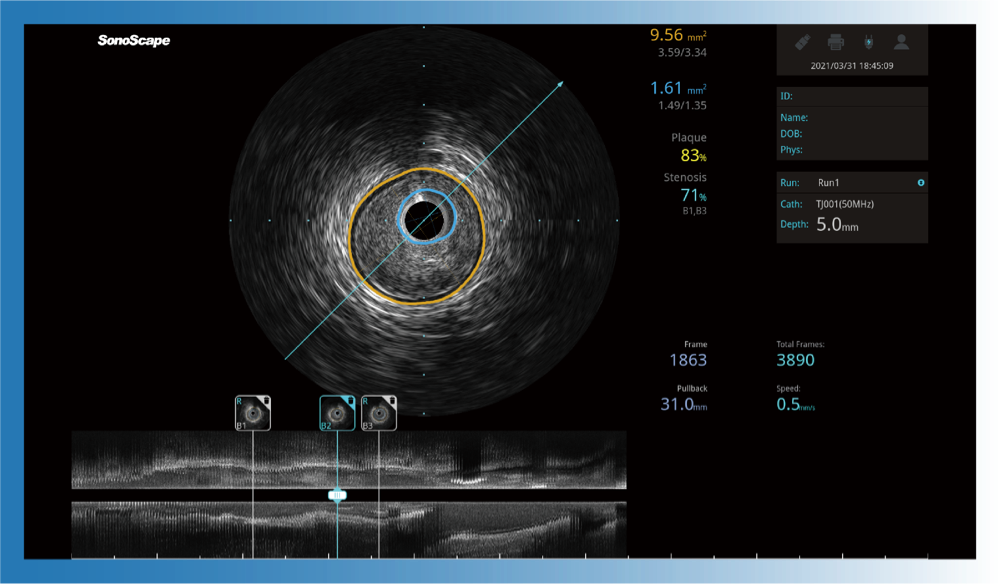

球速体育入口宽频IVUS图像

传统IVUS图像

对比传统IVUS导管成像,球速体育入口宽频IVUS图像的近场支架梁显影更细腻,远场中膜外血管仍清晰可辨,兼顾远中近,兼顾分辨力与穿透深度

一键智能描迹,自动测量斑块负荷、面积狭窄率等指标,准确率高于90%